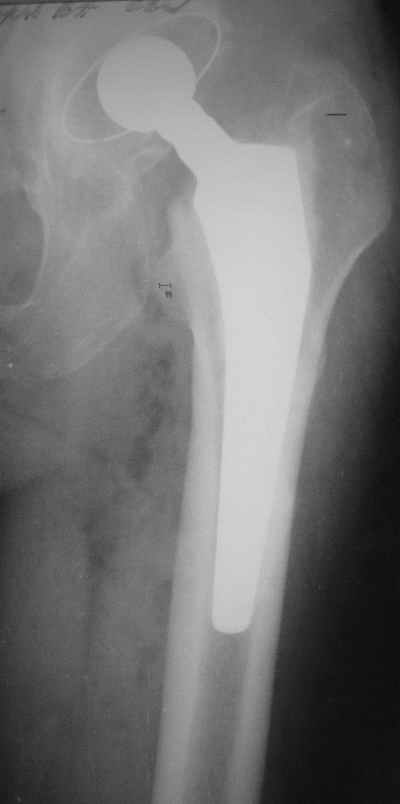

Уважаемые коллеги,Мужчина, 69 лет, в декабре 2004 г перенес тотальную цементную артропластику . Через 3 мес после операции на фоне прогрессирующих болей в средней и проксимальной третях бедра при нагрузке возникли резкие боли и появилось опухолевидное болезненно образование. Процесс сопровождался резким одномоментным укорочением ноги.

В феврале 2005 г. выполнена ревизионная артропластика, завершившаяся прогрессировавшим в течение 1-2 мес укорочением ноги. В настоящее время ходит только с костылями, при движениях в тазобедренном суставе испытывает резкие боли, ощущает хруст. Попытка осевой нагрузки бедра сопровождается ощущением "перемещения поршня" и заметным по внешним ориентирам укорочением левой ноги на 1-1,5 см.

Наверное перфорация стенки при первичном протезировании и неадекватный размер Вагнера при ревизионном? Что-нибудь еще?

И ножка Вагнера подобра плохо, и насчет возможной инфекции Вы совершенно правы, т.к. рана после второй операции заживала вторичным натяжением.

К сожалению, Р-граммы не захватывают полностью бедро, поэтому окончательное решение может быть после полноценного р-ского обследования. Однако думаю, что оптимальное решение - полнопокрытая ножка длинной не менее 200 мм, без привязки к типу протеза. Это может быть модульная система ZMR, Solution и др., главное - принцип. В отношении чашки тоже есть определенные сомнения. Думаю, что наш ин-т (РосНИИТО, СПб) смог бы сделать эту операцию.

Ситуация достаточно несложная. Основной массив бедренной кости сохранён. Лучше поменять чашку сразу, потому что ей не долго осталось жить. Слишком латерально поставлена. Предпочитаю RM чашки при ревизии. Ножка предпочтительней Solution. Если есть проблемы по замене, могу взять к себе без проблем.